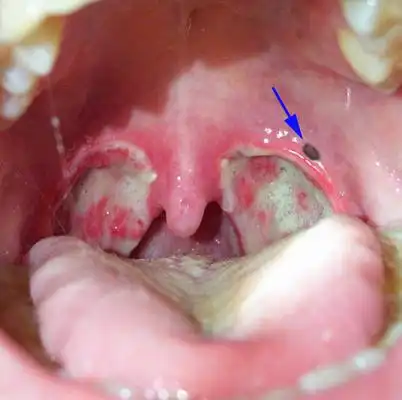

【双眼皮修复术后10天】这次做完双眼皮恢复的真的好_圈子-新氧美容